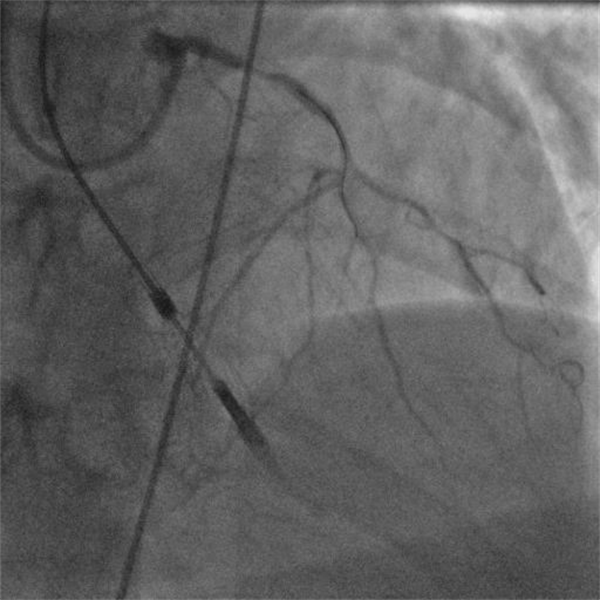

復(fù)查造影提示支架擴(kuò)張滿意,第一對角支殘余狹窄<30%,前降支中段至遠(yuǎn)段無殘余狹窄,TIMI血流3級。手術(shù)過程流暢,NyokAssist®操作便捷,過弓、跨瓣性能優(yōu)異,術(shù)中患者血壓平穩(wěn),心超顯示介入泵位置良好穩(wěn)定,主動脈瓣及二尖瓣未見反流加重。